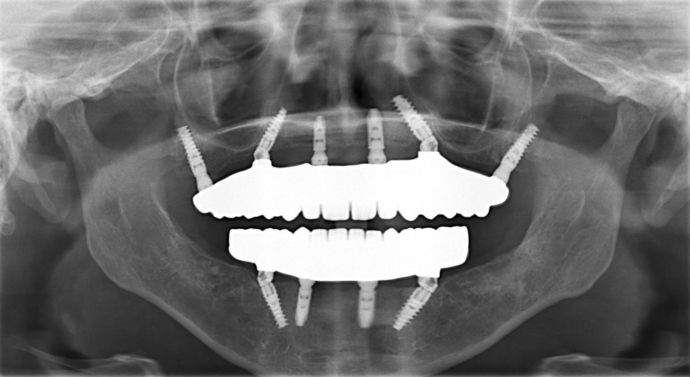

All-on-4/ Full Mouth Dental Implants / Teeth in a Day: Case 9-WA- Upper and lower All-on-4 bridges

Procedures : extractions, implants, All on 4 , Teeth in a day, no bone grafting, gummy smile correction and full mouth reconstruction with monolithic zirconia bridges.